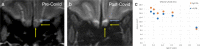

As the global COVID-19 pandemic evolves, our knowledge of the respiratory and non-respiratory symptoms continues to grow. One such symptom, anosmia, may be a neurologic marker of coronavirus infection and the initial presentation of infected patients. Because this symptom is not routinely investigated by imaging, there is conflicting literature on neuroimaging abnormalities related to COVID-19-related anosmia. We present a novel case of COVID-19 anosmia with definitive olfactory bulb atrophy compared with pre-COVID imaging. The patient had prior MR imaging related to a history of prolactinoma that provided baseline volumes of her olfactory bulbs. After a positive diagnosis of COVID-19 and approximately 2 months duration of anosmia, an MRI was performed that showed clear interval olfactory bulb atrophy. This diagnostic finding is of prognostic importance and indicates that the olfactory entry point to the brain should be further investigated to improve our understanding of COVID infectious pathophysiology.